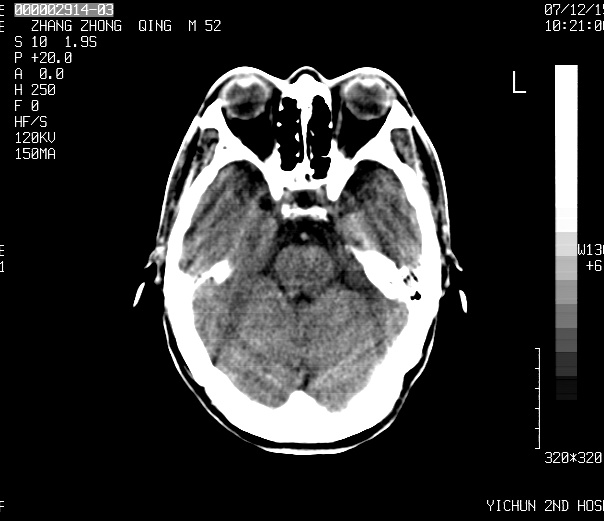

不知ct值约多少,考虑四叠体池内脂肪瘤.

不知ct值约多少,考虑四叠体池内脂肪瘤.支持!

四叠体池脂肪瘤可能

1、四叠体脂肪瘤;

头痛二年余,ct值-86.8hu.

四叠体池脂肪瘤

考虑:1、四叠池区脂肪瘤(比较常见)。